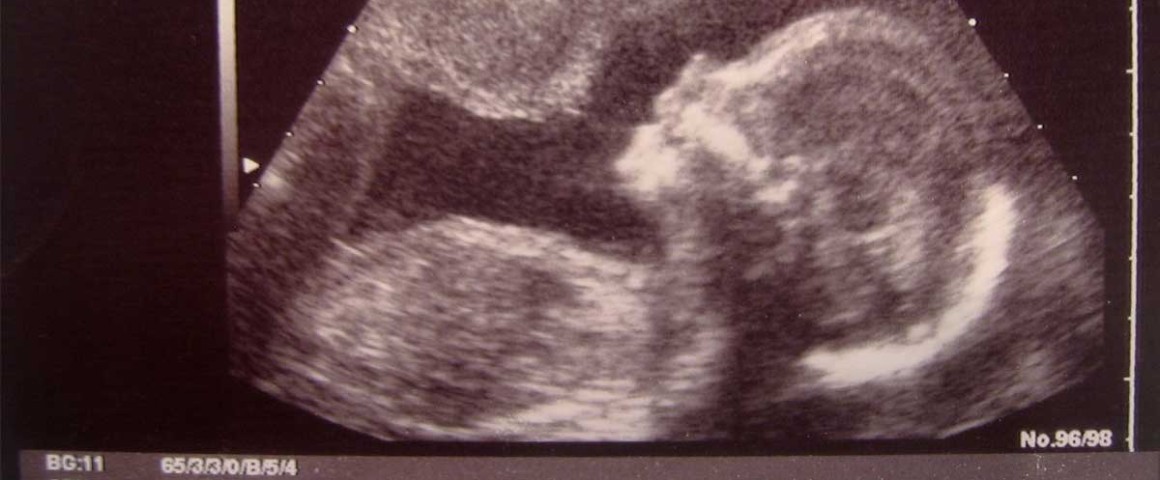

Introduced in June by Sen. Lindsey Graham (R-SC) the measure would ban most abortions after 20-weeks. The bill passed the House in May with a bipartisan margin of 242-184.

“The standard of medical practice today in America is that if you operate on an unborn child at 20 weeks…you have to provide anesthesia to the baby,” Graham said according to a report from LifeSiteNews. “If a doctor is required to provide anesthesia to a child to help save his life because they feel pain in the process of being operated on, is it okay for society to say, ‘Well, at that stage in the pregnancy, we don’t want the operation to be an abortion’? I believe most Americans will say yes.”